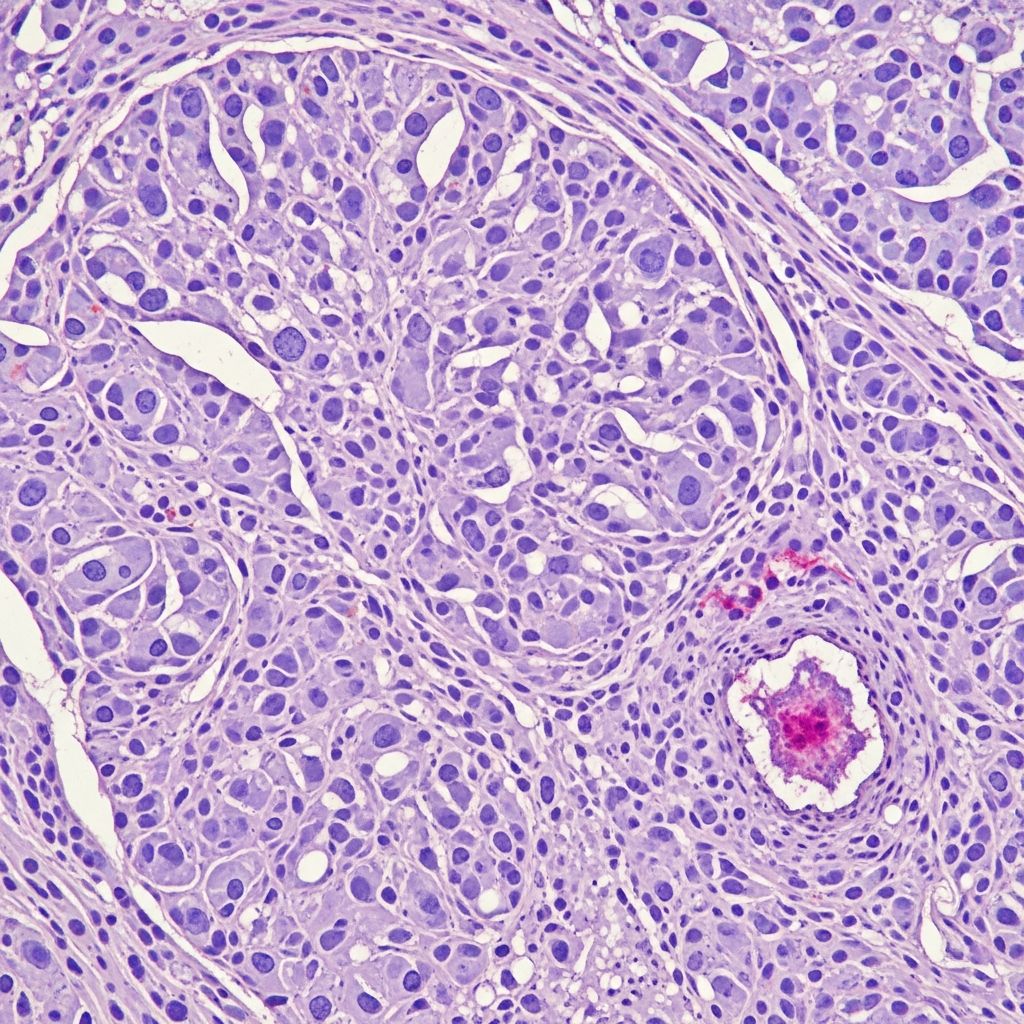

Histopathology

Microscopically, fibrosarcoma displays poorly circumscribed infiltrative growth of uniform spindle cells arranged in long sweeping fascicles with a characteristic herringbone pattern, reminiscent of skeletal muscle. Cells have elongated nuclei with tapered ends, scant cytoplasm, and minimal pleomorphism in low-grade forms. Collagen bands separate fascicles. Mitotic activity varies (5–20/10 HPF), with atypical forms in high-grade tumours. Necrosis is focal; myxoid change or giant cells may occur. Infantile variants show higher cellularity and mitoses but behave indolently. Fibrosarcomatous transformation in DFSP (10–20% cases) features higher-grade herringbone areas with necrosis and increased mitoses (>10/10 HPF).

The tumour permeates dermis and subcutis in a lattice-like pattern, sparing epidermis. Deep extension to fascia/muscle is common in recurrences. Grading relies on mitotic rate, necrosis, and pleomorphism: low-grade (<5 mitoses/10 HPF, no necrosis); high-grade (>10 mitoses/10 HPF, necrosis present).

| Feature | Low-Grade Fibrosarcoma | High-Grade Fibrosarcoma |

|---|---|---|

| Mitotic rate | <5/10 HPF | >10/10 HPF |

| Necrosis | Absent | Focal/extensive |

| Pleomorphism | Mild | Marked |

| Pattern | Fascicular | Herringbone + atypia |